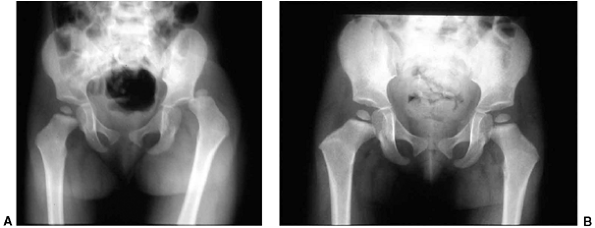

![]() |

|

Figure 33.5 Physeal bar resection. A: A distal physeal bar is depicted in this anteroposterior hypocycloidal tomogram. B:

This condition was treated with bar excision and insertion of Cranioplast. Five months later, the physis remains open, and the two metal markers inserted at the time of surgery are 28 mm apart. There is residual femoral tibial valgus deformity. C: Four years later, there has been some improvement in the femoral tibial alignment, and growth of the distal femur has resumed. The markers are 83 mm apart. |